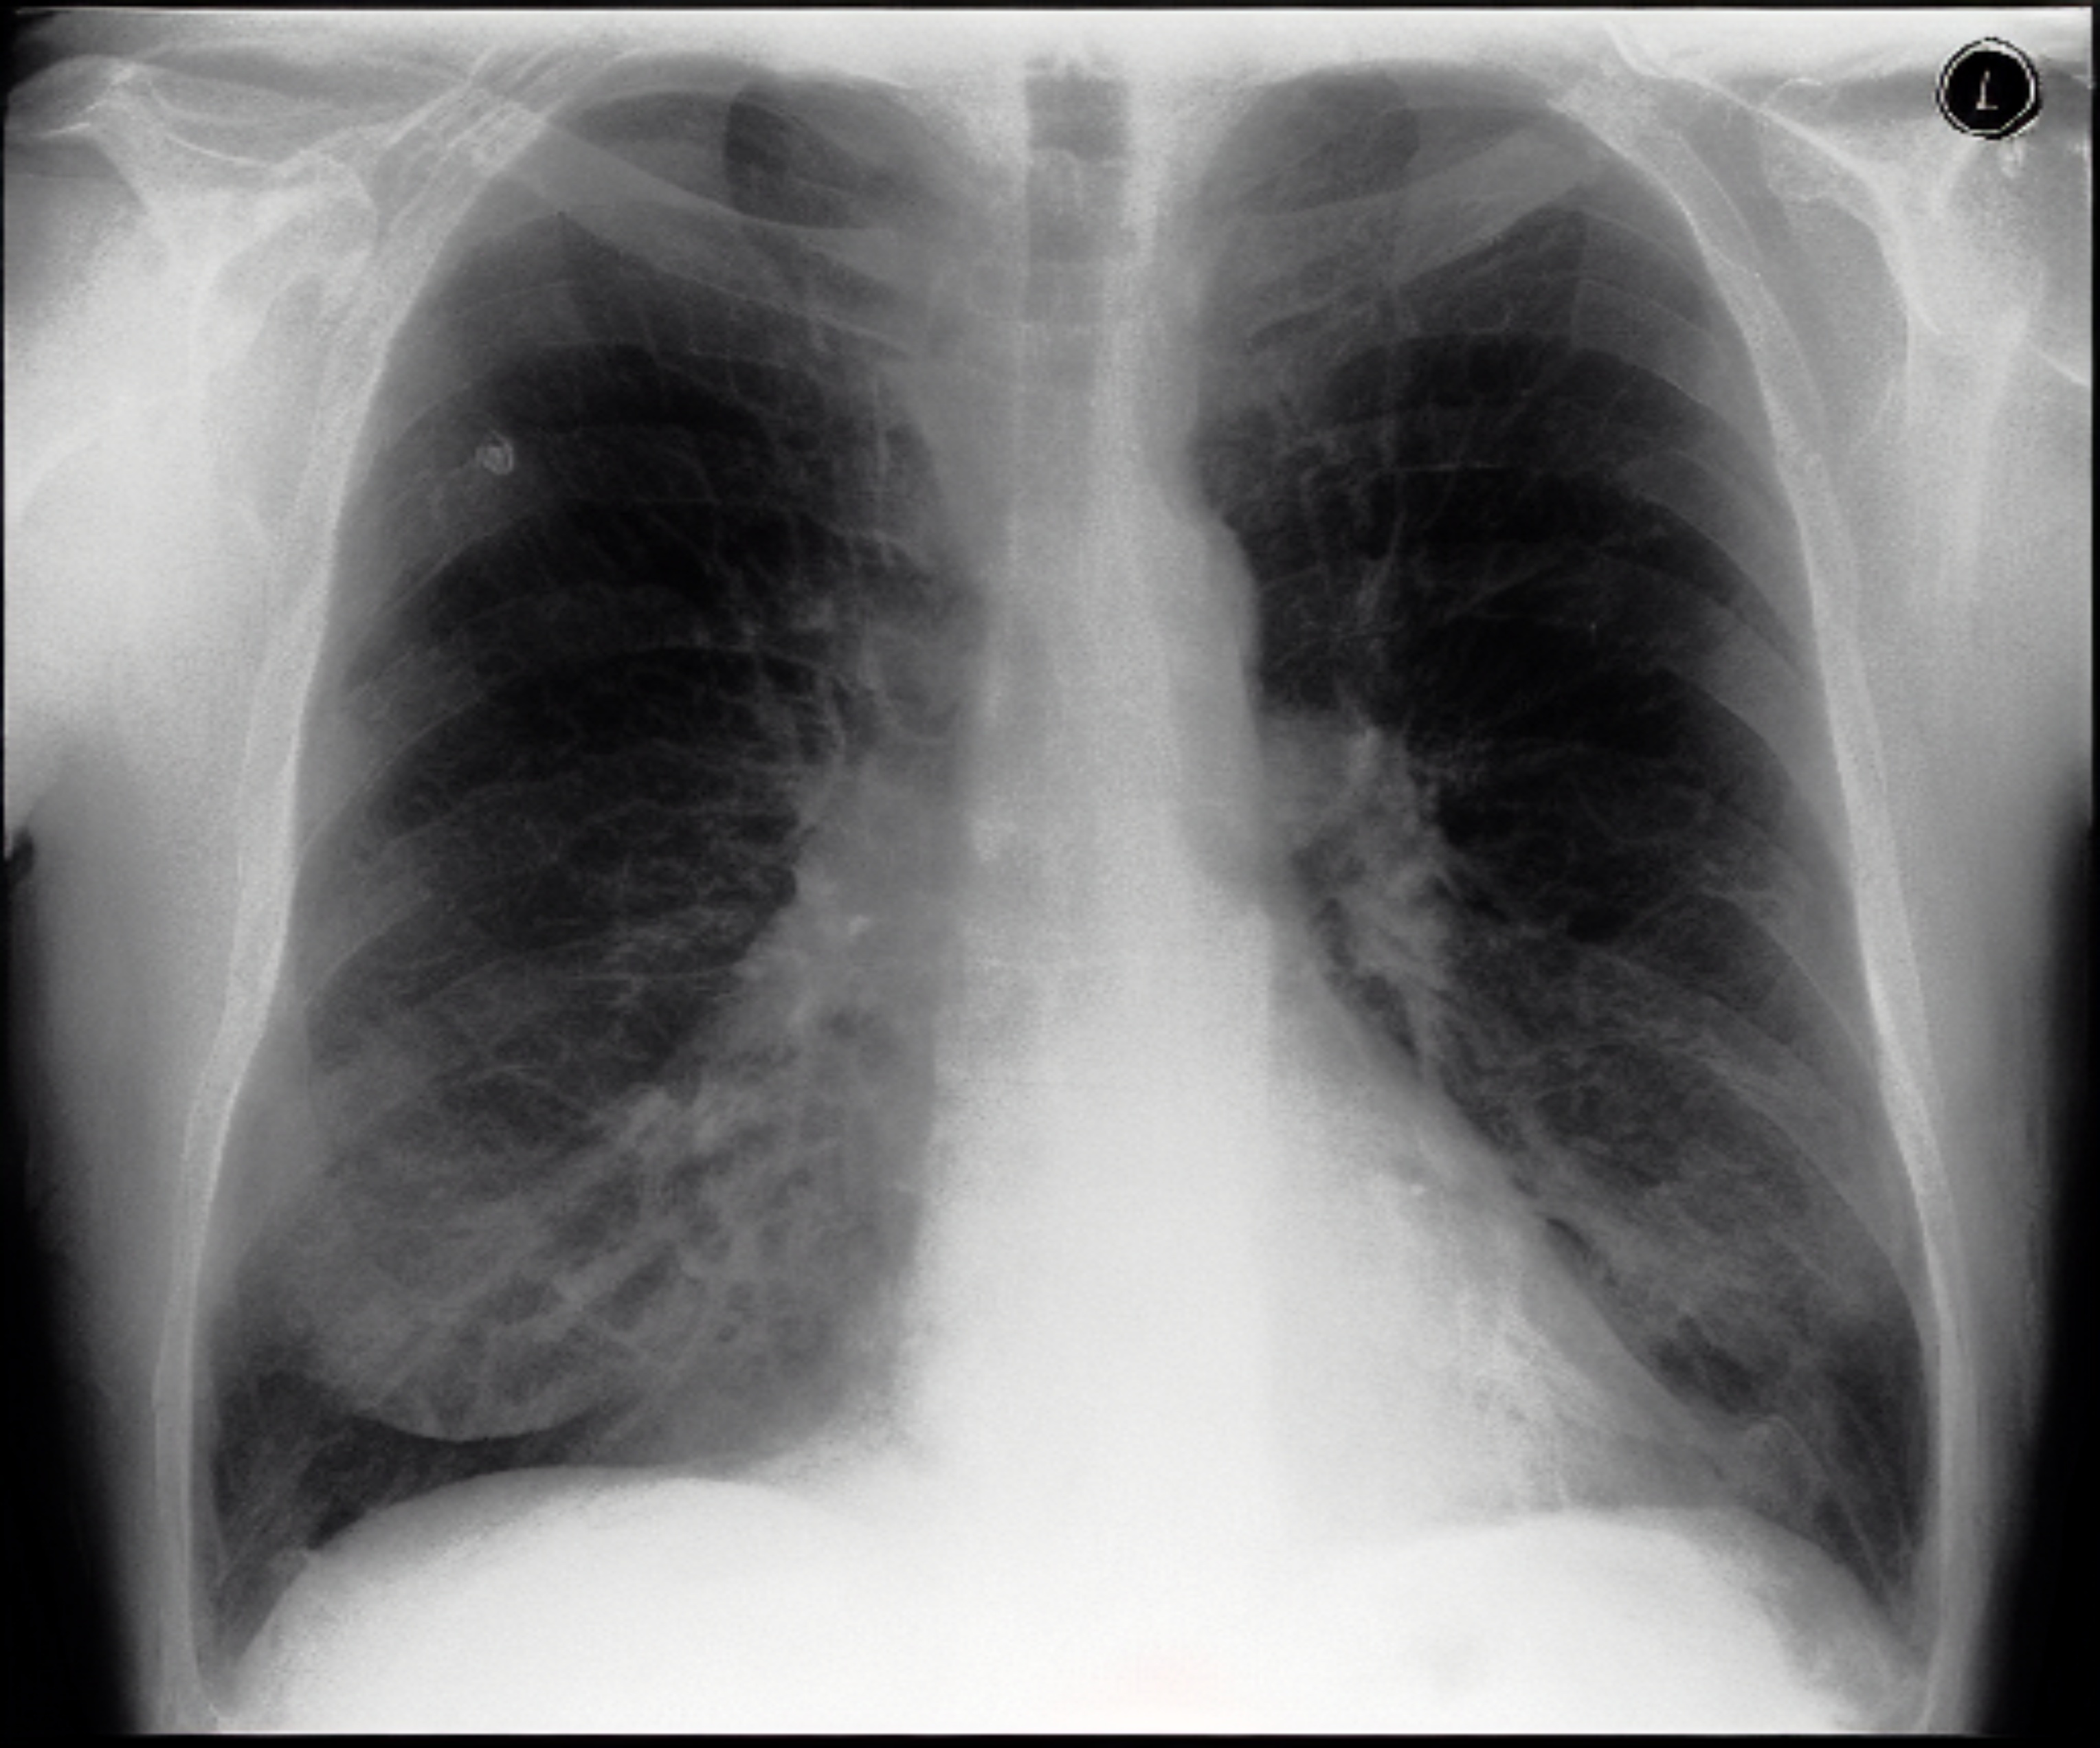

Table 1: Sample chest X-ray (CXR) images. The top row shows a normal CXR, while the remaining rows display CXRs with various pathologies, including right-sided cardiomegaly, large pneumothorax, viral pneumonia, and pulmonary edema.

Normal Chest X-ray Image

[Uncaptioned image]

Right-sided Cardiomegaly Large Pneumothorax

[Uncaptioned image] [Uncaptioned image]

Virus Pneumonia Pulmonary Edema